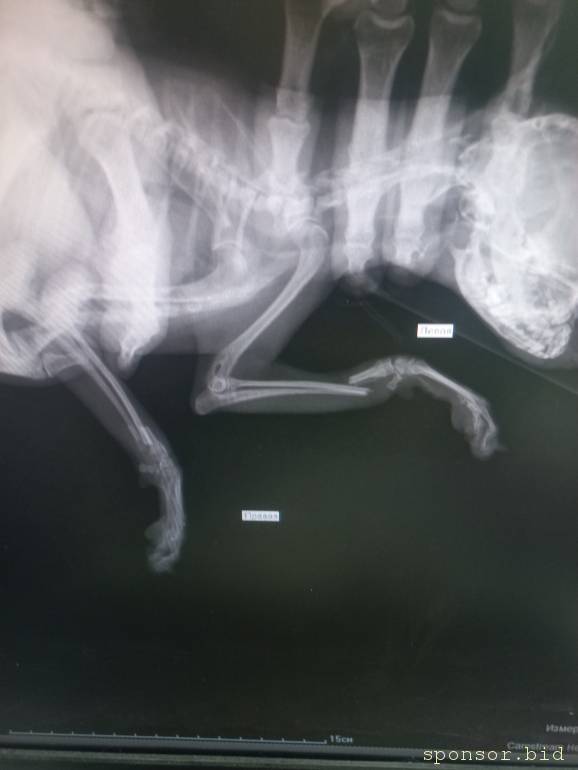

🆘🆘🆘 ПОМОГИТЕ ОПЛАТИТЬ ОПЕРАЦИЮ! Маленький той , сломала две передних лапки. Лапки просто отломленный, болтаются. Срочно нужно прооперировать🤧Стоимость такой операции 28.000 тыс рублей, одна лапка 12-14 тыс ((((( Друзья, помогите поставить девочку на лапки 🙏🏻🙏🏻🙏🏻

Помогите сохранить лапки тойчику 128591; - 20230430_153848.jpg